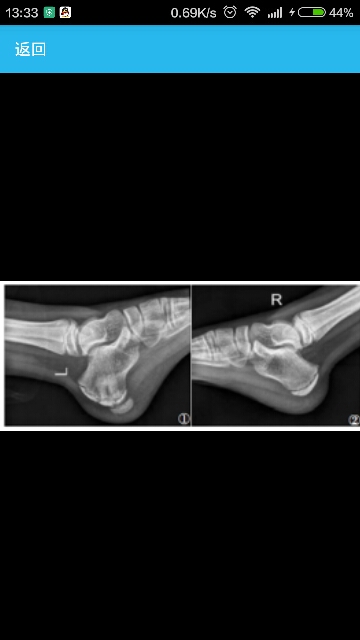

男 9岁,发现左跟骨肿物半年余,行走后疼痛不适,诊断为左跟骨骨软骨瘤,建议手术治疗。 病史1年前有轻微外伤史,未做特殊处理,半年前左跟骨底出现一硬物,行走后疼痛加重,无夜间痛。 左跟骨未见明显红肿,皮温不高,可触及骨性突起,呈卵圆形,质硬,边界清晰,推之不移,有压痛,足踝关节活动功能未见明显异常,神经感觉功能活动正常。 图1 左跟骨侧位可见跟骨底骨骺下方帽状骨性组织图2右足跟骨侧位为正常骨组织图3 左跟骨CT 三维重建示:右跟骨底骨骺下方凸起帽状组织。 CT三维重建示:左足跟部可见一扁平帽状骨化,约1.0cm×2.6cm大小,左跟骨结节骨骺核较对侧扁平,密度不均,部分骺线变窄甚至消失,左足跟骨后部可见片状骨质硬化,边缘模糊(图3)。MRI示左侧跟骨后份见不规则长T1短T2信号,跟骨结节骨骺扁平似碎裂,信号欠均匀,骺线信号尚可,其右下方见一不规则长T1短T2信号,SPAIR像为略高信号,大小为2.8cm×1.3cm,边界清晰,跟腱形态、信号未见明显异常。 诊断:左跟骨骨软骨瘤 治疗:手术在硬膜外加局部麻醉下行左跟骨骨软骨瘤切除术,取左跟骨内侧长约7cm切口,分离各组织,然后显露跟骨底部骨性突起部分,大小约为4cm×2cm×1cm,通过C型臂透视机透视下克氏针定位肿物边界,然后将肿物全部切除,肿物未见头帽状凸起,呈松质骨样。病理诊断为左跟骨骨软骨瘤。患肢功能感觉及血运未见明显异常。